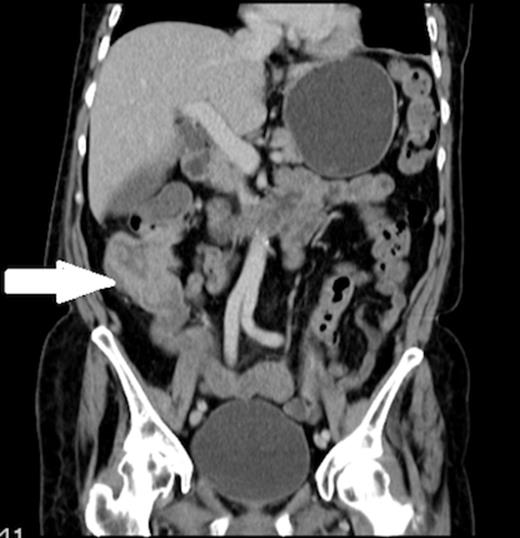

Urine microscopy was normal but blood cultures taken on the day of admission grew Escherichia coli (E. coli) and this, coupled with iron deficiency anaemia prompted a search for other pathology and a CT scan of chest, abdomen and pelvis showed thickening of the ascending colon (figures 2 and 3). A colonoscopy confirmed a fungating lesion in the mid-ascending colon and biopsies showed adenocarcinoma of the colon. Our patient then had a laparoscopic right hemicolectomy followed by adjuvant chemotherapy for a moderately differentiated adenocarcinoma (pT4 N2 V1 R0 M0). Her discitis settled with antibiotic treatment.

Coronal view of the CT abdomen showing thickening of the ascending colon (indicated by arrow).